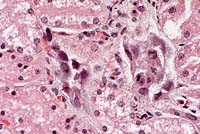

Case 14-1b. Kidney. Cortical tubule epithelium is necrotic and often contains basophilic nuclear inclusions. 40X

2. Kidney, tubules: Degeneration, necrosis, and regeneration, multifocal, with cellular casts and intranuclear amphophilic to basophilic inclusion bodies.

3. Kidney: Nephritis, interstitial, chronic, multifocal, minimal.

Scattered collecting tubules in the inner cortex and medulla of the kidney are lined by hypertrophied epithelial cells containing intranuclear inclusion bodies. These necrotic lining cells desquamate into the tubular lumina and form cellular casts.

1. Kidney: Tubular degeneration and necrosis, multifocal, moderate, with multifocal, mild, interstitial, subacute nephritis and numerous, basophilic, intranuclear inclusions.